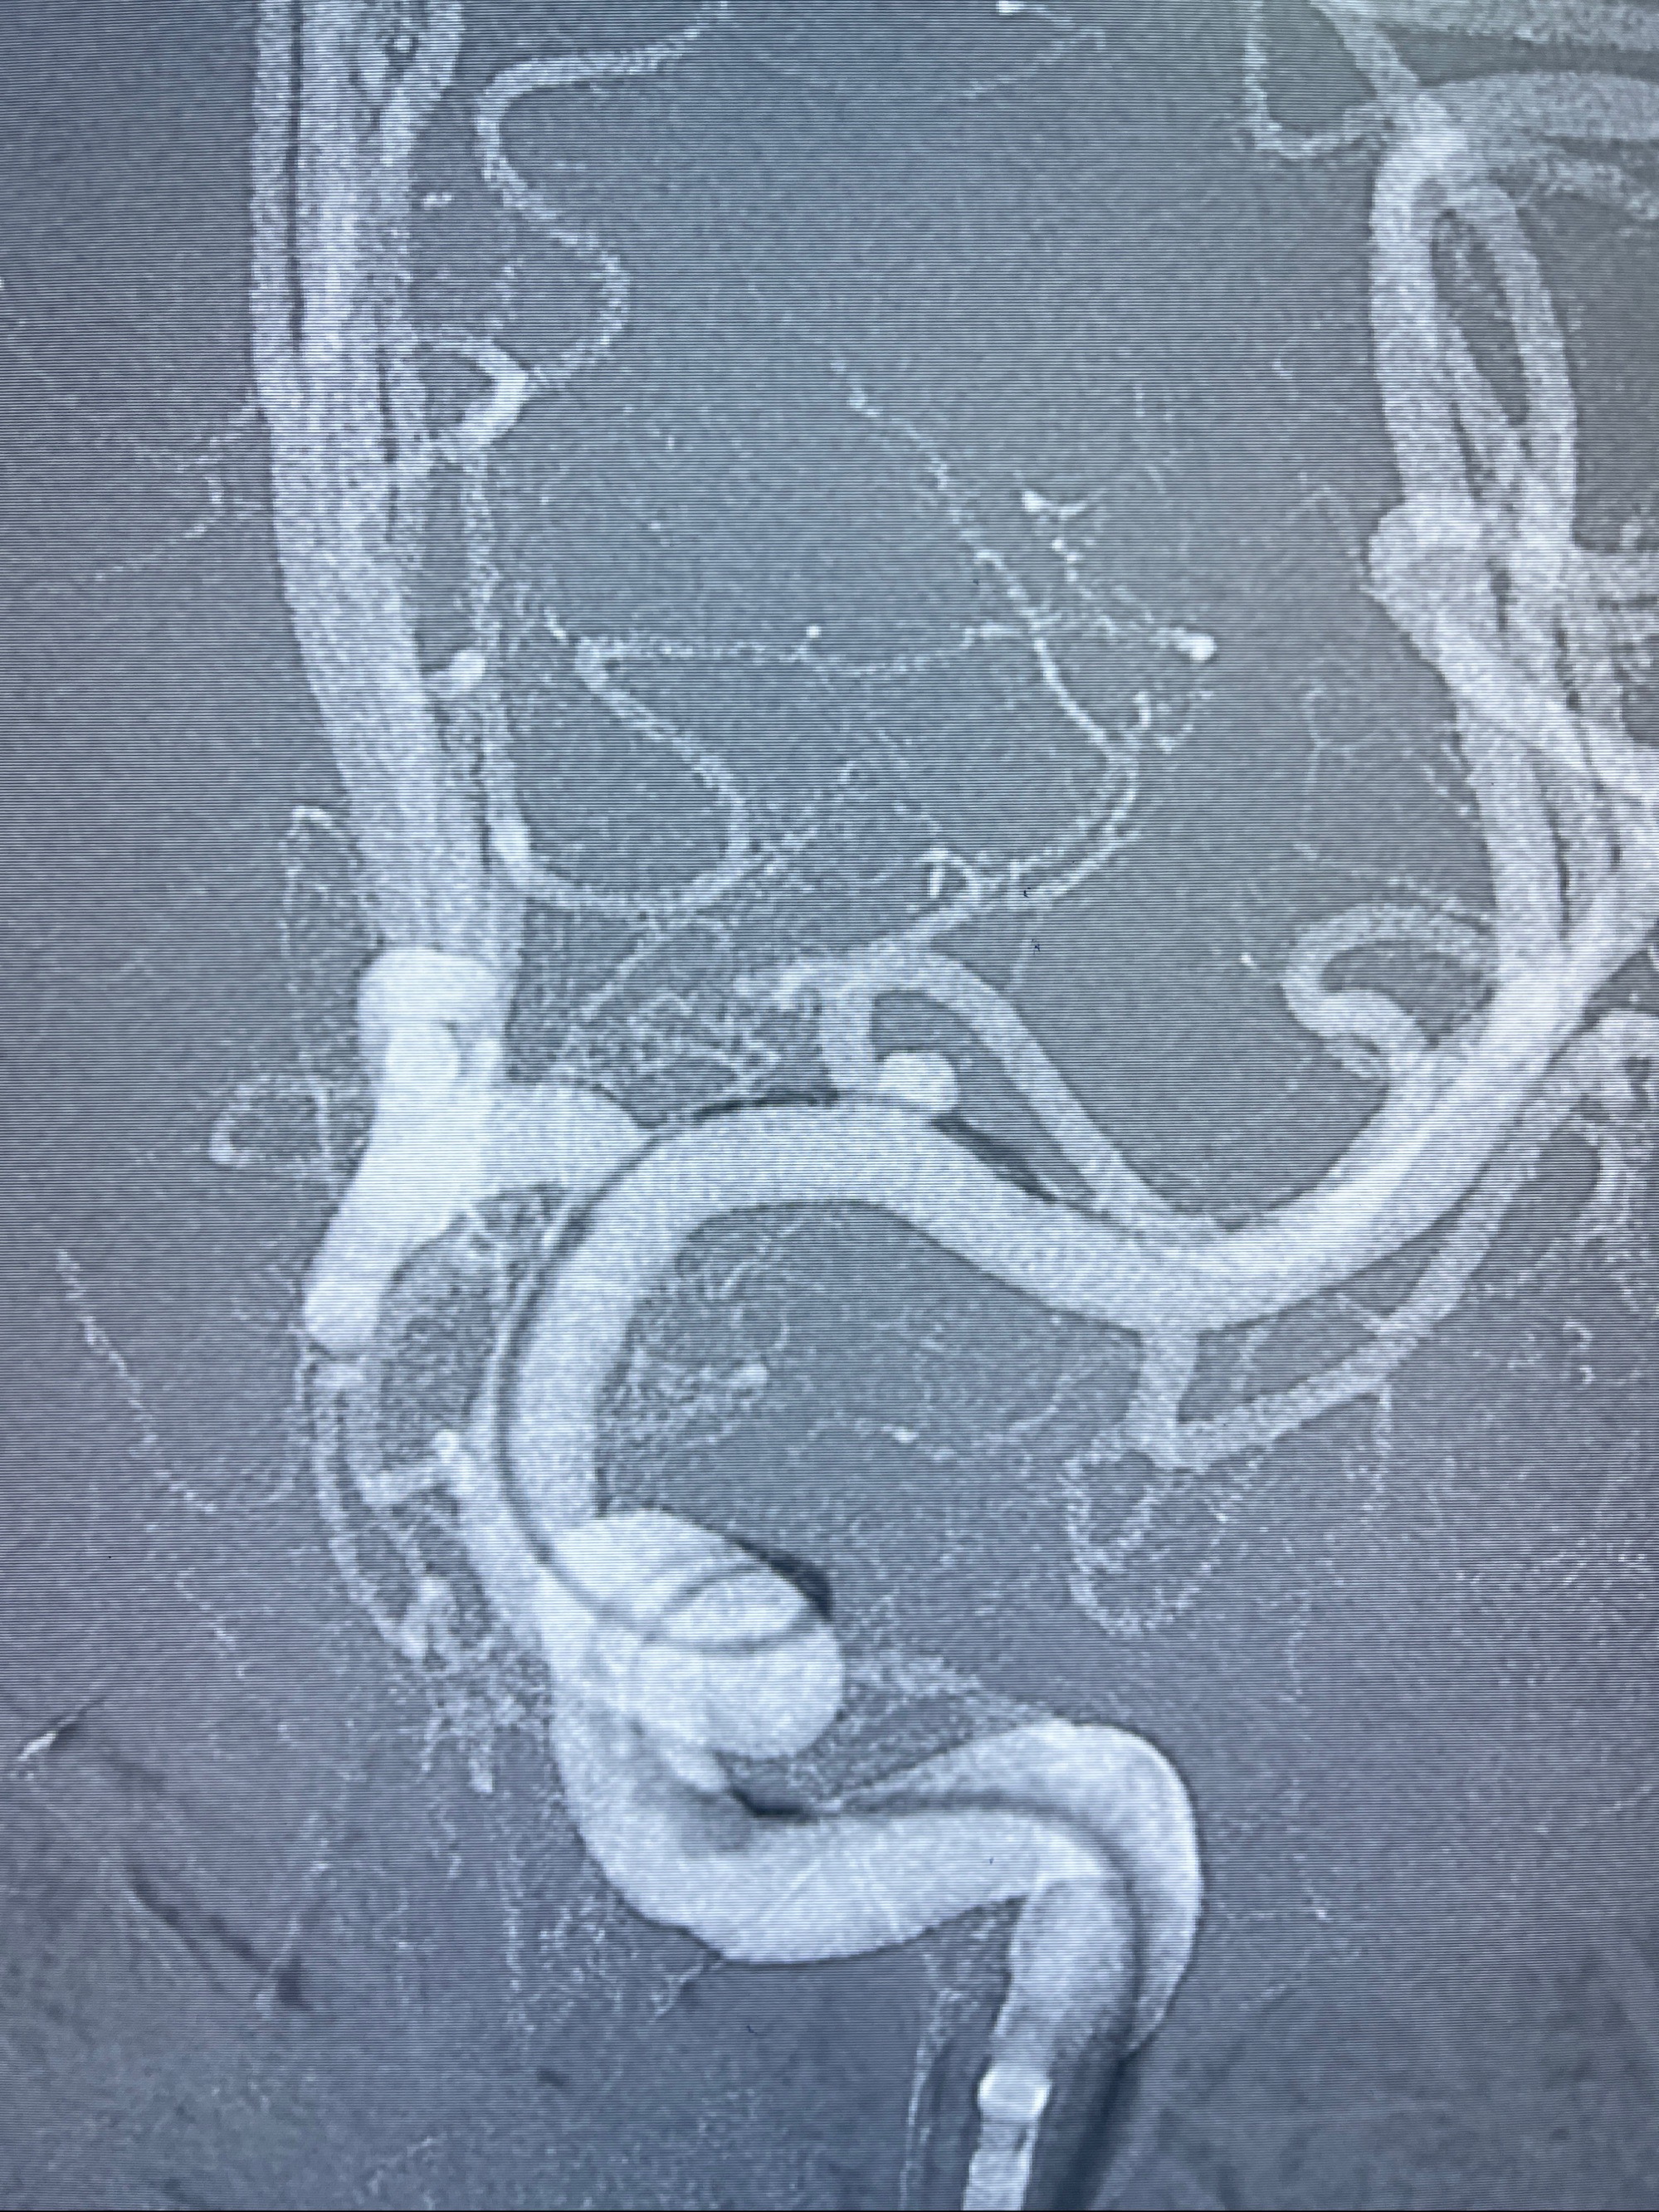

2023-08-14DSA:

左侧大脑中动脉动脉瘤,约2.6-2.8-3.4-2mm大小(瘤颈部、瘤体部、瘤高)

治疗策略:

1.左侧大脑中动脉动脉瘤,约2.6-2.8-3.4-2mm大小(瘤颈部、瘤体部、瘤高)

2.外科手术夹闭or介入支架辅助栓塞